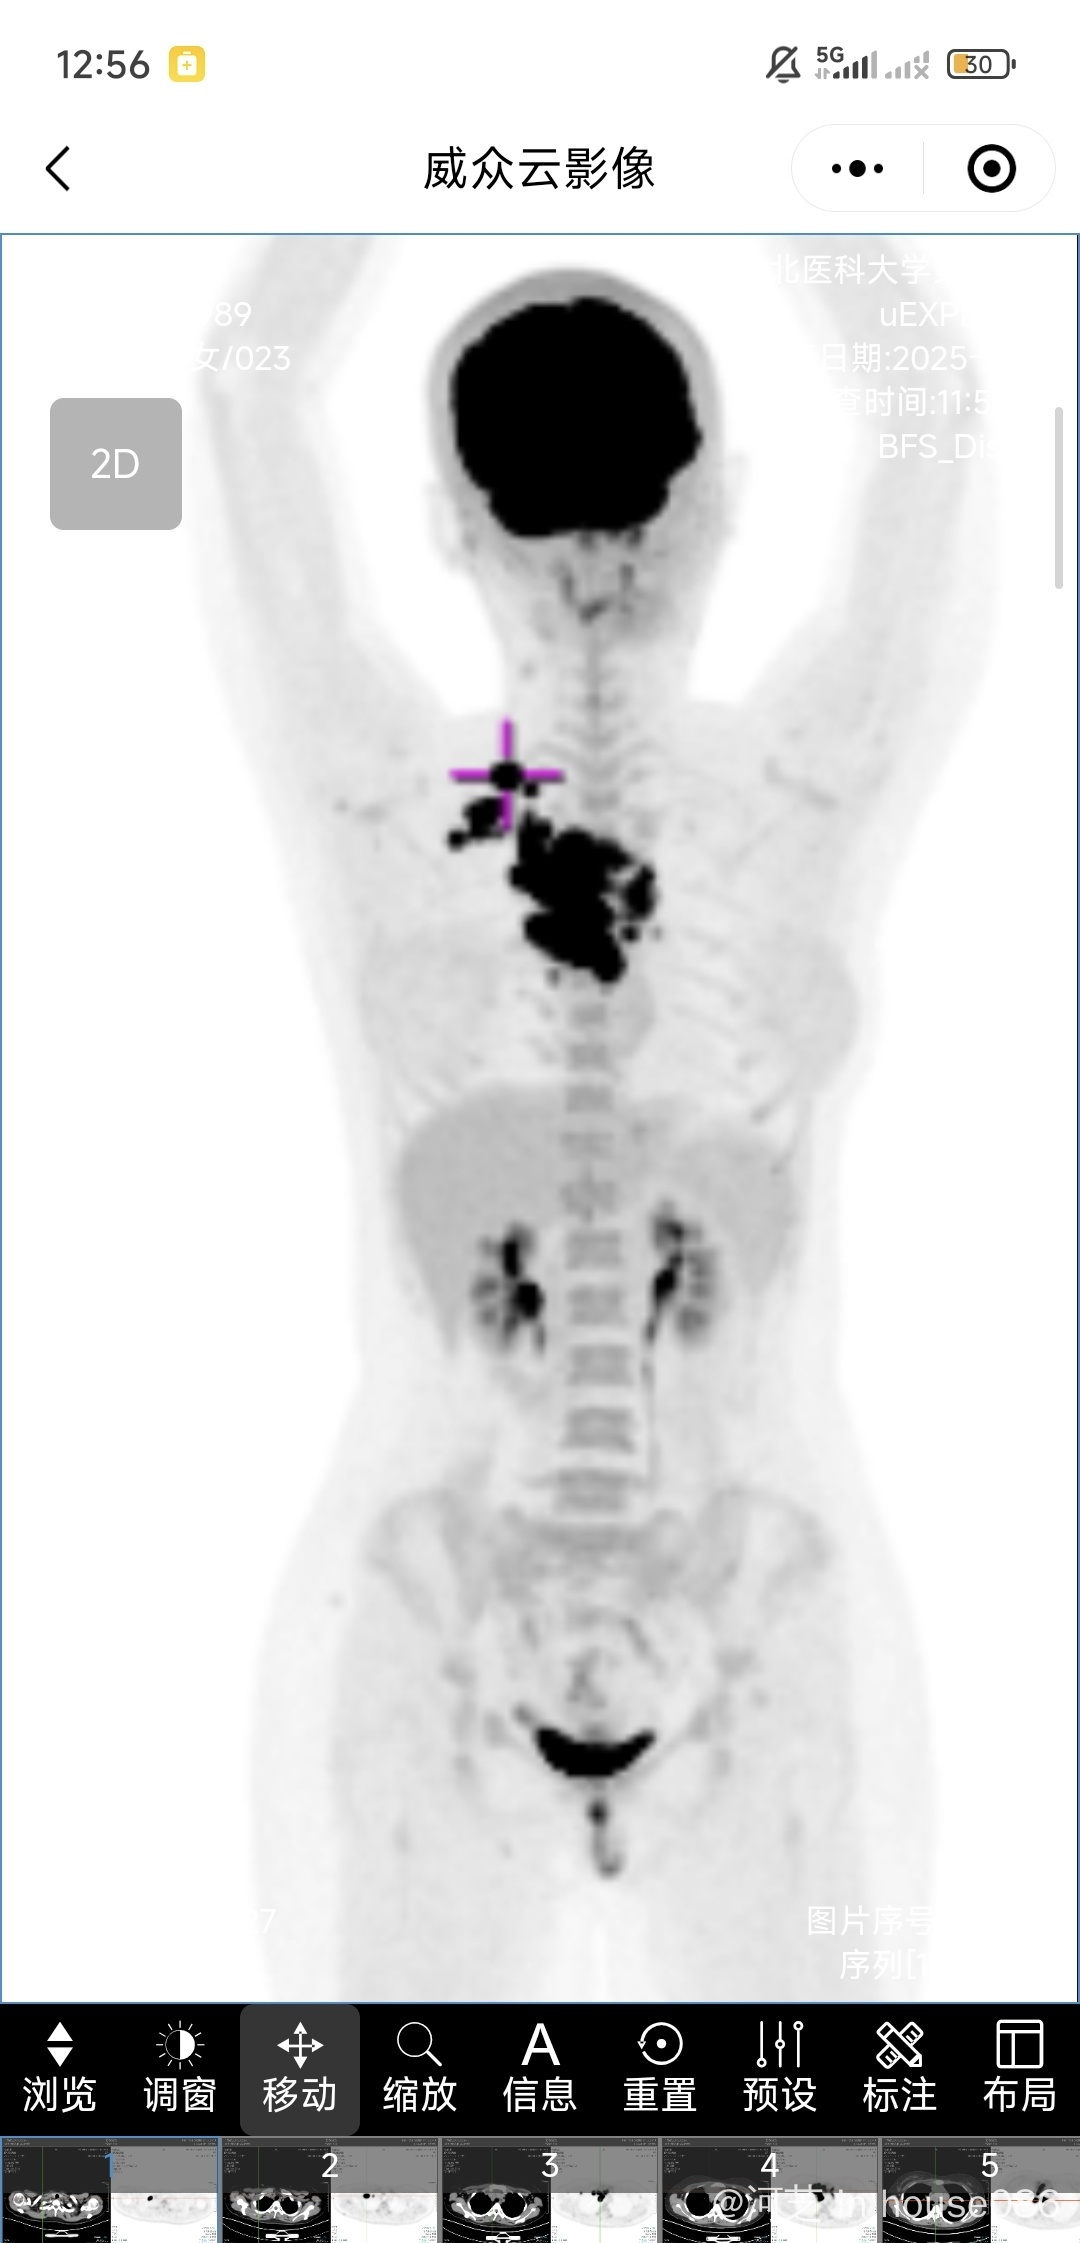

弥漫大b淋巴瘤长在纵隔位置,12.19日北京友谊初步病理报告23-,10- ,30+。1月7日变为10+ 30-。病理报告没说是原发纵隔,二疗前做了基因检测,自己看报告有很多有关pmbl的突变。目前方案是polohichp,但我看很多原发纵隔使用的是darepoch方案,请问是否需要按照原发纵隔换方案治疗。现在这个方案强度后续够吗,是否还得进行放疗和移植?求助雨丝大神@橙色雨丝

从基因突变的情况来看,符合原发纵隔大B,DA-EPOCH-R更好一点,有较大可能可以省略放疗,但是既然已经开始治疗,再换方案似乎意义也不大。原发纵隔大B初治顺利的话不需要移植巩固。